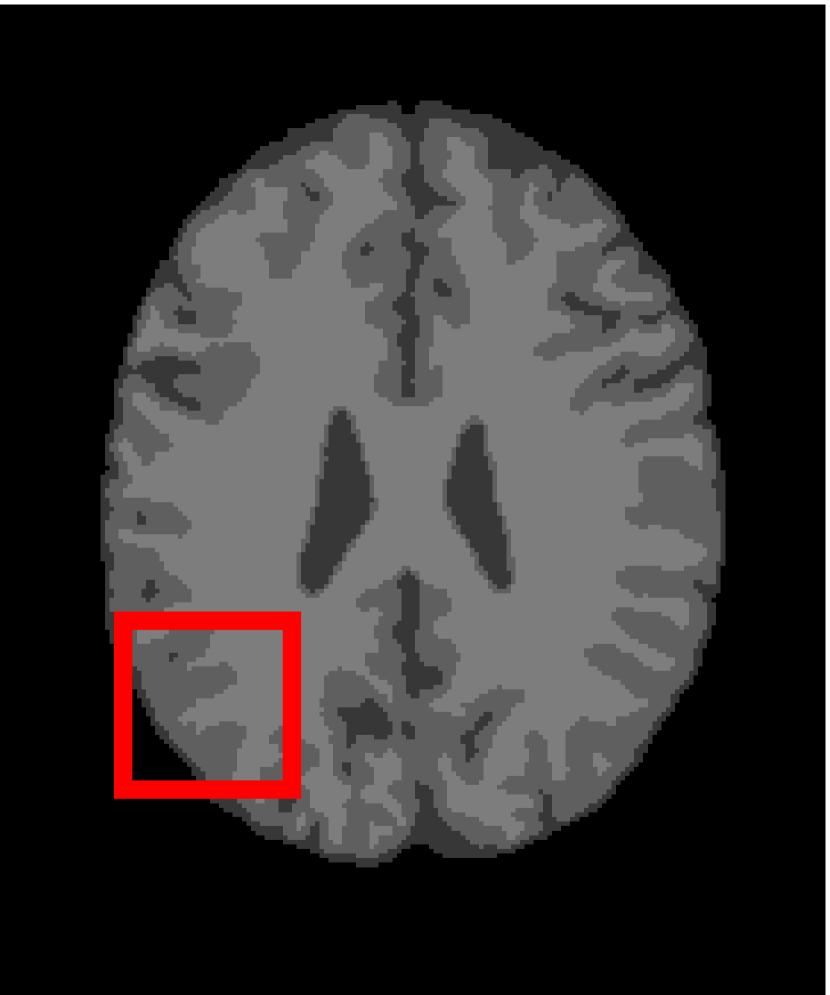

In the second experiments, we segment two medical images coming from a simulated brain database (BrianWeb): http://www.bic.mni.mcgill.ca/brainweb/. The two images are generated by T1 modality with slice thickness of 1mm resolution, 9% noise and 20% intensity non-uniformity. Here, the two images are represented two slices in the axial plane with the sequence of 100 and 110. Moreover, there are golden standard segmentations in the dataset. We set the numbers of clusters to 4. The visual comparisons are illustrated in Figs. 6 and 7.

Figure 6: Segmentation results for the first medical image. From (a) to (l): ground truth, noisy image and results of FCM_S1, FCM_S2, FGFCM, FLICM, KWFLICM, ARKFCM, FRFCM, WFCM, DSFCM_N, and LRFCM.

By focusing on the marked red square in Figs. 6 and 7, we easily find that FCM_S1, FCM_S2, FGFCM and ARKFCM are sensitive to noise. FLICM and KWFLICM are vulnerable to severe intensity inhomogeneity. FRFCM brings overly smooth results due to the use of gray level histograms. WFCM and DSFCM_N cause several contours to change. However, LRFCM acquires clear contours and suppresses noise adequately. Moreover, we find that the segmentation result of LRFCM is closer to ground truth.